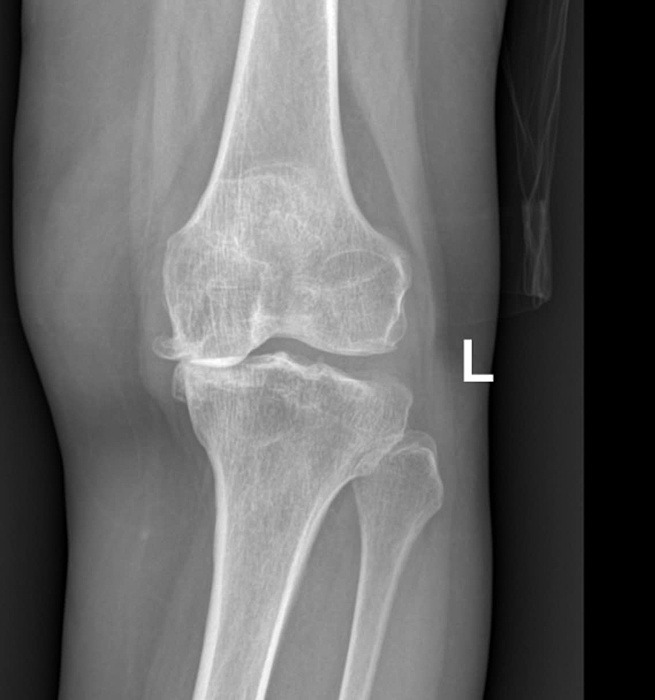

Old  Default Nguyên nhân gây thoái hóa khớp

Thừa cân, chấn thương, tập thể dục quá mức hay ít vận động là những nguyên nhân gây ra hoặc thúc đẩy thoái hóa khớp diễn ra nhanh, nghiêm trọng hơn.

Sụn khớp là lớp đệm bao phủ bề mặt xương, cấu tạo từ tế bào sụn và chất căn bản. Sụn khớp có chức năng bảo vệ, giảm ma sát trong khớp và đóng vai trò như "bộ giảm xóc". Sụn và các mô xung quanh khớp bị tổn thương được gọi là thoái hóa khớp.

ThS.BS Phạm Thị Xuân Thư, Đơn vị Nội cơ xương khớp, Phòng khám Đa khoa Tâm Anh Quận 7, cho biết thoái hóa khớp là một phần của quá trình lão hóa tự nhiên. Khi tuổi tác ngày càng cao, sụn khớp có xu hướng mỏng dần, dịch khớp có tác dụng nuôi dưỡng sụn và bôi trơn khớp ngày càng giảm cả về số lượng lẫn chất lượng. Khi tình trạng này diễn ra trong thời gian dài, sụn khớp dễ bị tổn thương, gây bong nứt sụn, gia tăng ma sát giữa khớp, dẫn đến đau và thoái hóa.

Chấn thương: Đây là nguyên nhân có thể trực tiếp làm tổn thương sụn khớp, dẫn đến thoái hóa. Chấn thương cũng có thể tạo điều kiện thuận lợi cho viêm khớp phát triển, làm tổn thương các cấu trúc mềm như dây chằng và gân. Nếu viêm kéo dài có thể làm hỏng sụn và xương, đẩy nhanh tốc độ thoái hóa khớp.